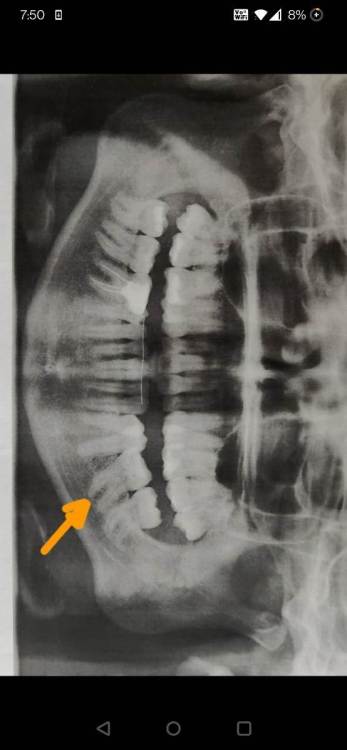

Здравствуйте! Носила брекеты 12 лет назад. Из-за сломанного ретейнера образовался перекрестный прикус. Плюс за это время выросли зубы мудрости. Хочу начать лечение с помощью элайнеров. Насколько это трудно двигать зубы мудрости и стоит ли вообще это делать? (Они в хорошем состоянии). В одной клинике прислали план по элайнерам. Есть сомнения... Подскажите, пожалуйста, стоит ли соглашаться на это или лучше снова брекеты? Спасибо!